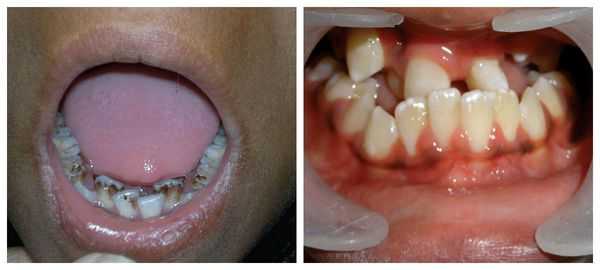

Перечисленные лицевые аномалии могут сопровождаться нарушением слуха, неправильной закладкой и прорезыванием зубов и другими нарушениями, которые могут повлиять на психофизическое развитие ребёнка.

В целом расщелины лица и/или нёба, недоразвитие верхней и нижней челюсти, лицевых мышц, скуловой и/или височной костей способны вызывать проблемы с зубами, трудности при кормлении, нарушение речи и изменение эстетических параметров лица.